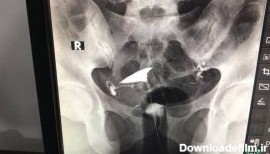

عکس رنگی رحم بدون درد؛ هیستروسالپنگوگرافی برای مشاهده داخل رحم و لوله های فالوپ استفاده می شود. می تواند نشان دهد که داخل رحم اندازه و شکل طبیعی دارد یا خیر.

یکی از روش های تشخیصی که برای بررسی رحم و لوله های رحمی انجام می گیرد هیستروسالپنگوگرافی یا عکس رنگی رحم است.اين عمل معمولا درمراکز راديولوژي انجام می گردد.

عکس رنگی رحم یا هیستروسالپنگوگرافی یکی از روش های تشخیصی شیوه ی تصویربرداری با اشعه ایکس است که معمولاً برای بررسی آناتومی رحم و لوله ها انجام میشود. عکس رحم